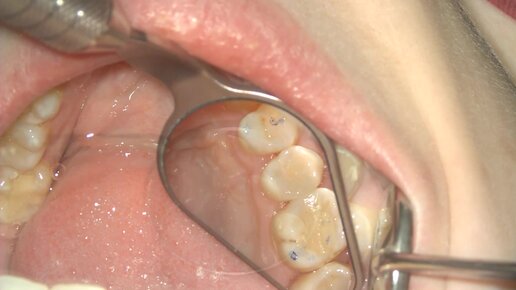

Лечение кариеса зуба 1.5 с использованием системы диагностики Soprolife

Лечение кариеса